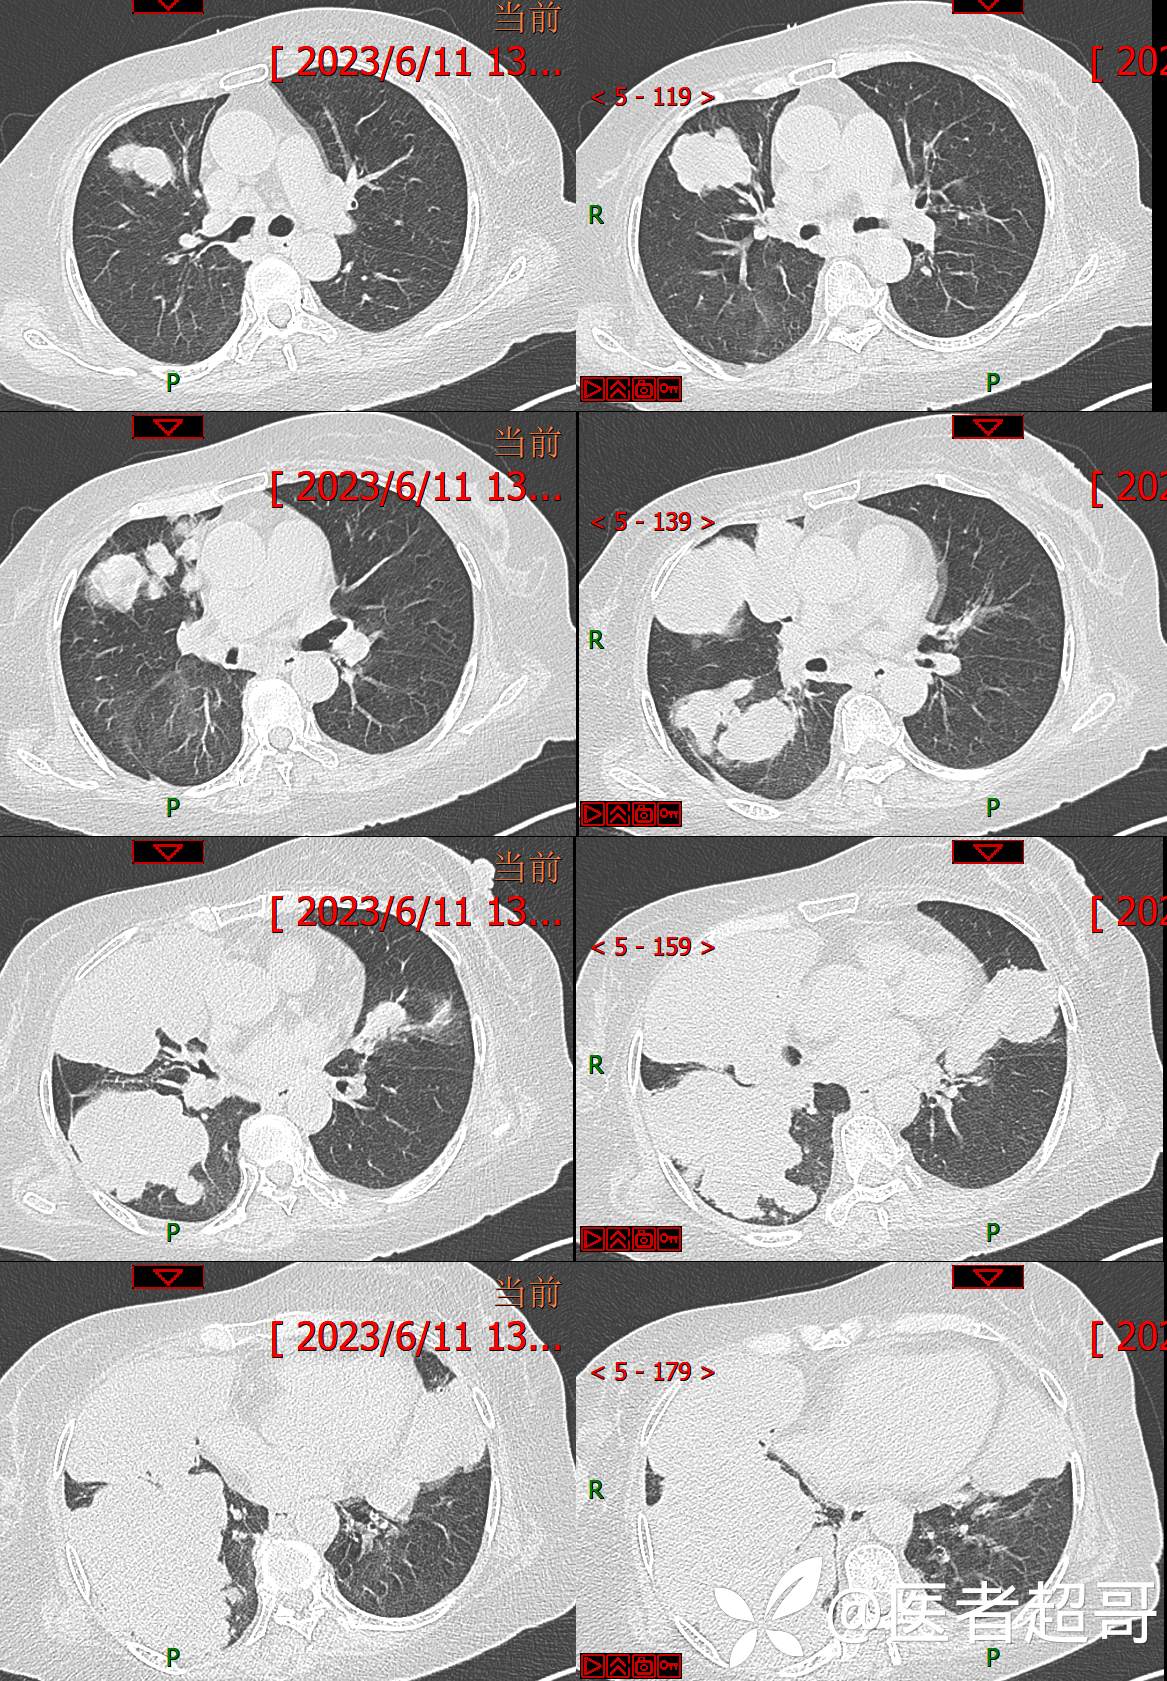

现病史:患者于4年前在神经内科住院期间监测血糖高,随机血糖29.4mmol/l,经治疗好转出院,出院诊断“锥体外系反应 2型糖尿病 感冒”,院外自行口服“二甲双胍 2片 bid,格列吡嗪胶囊 1粒 bid”降糖治疗,平素未规律监测血糖。约3年前感四肢麻木不适,无明显疼痛,无肢体活动障碍,未特殊治疗。7天前出现乏力、憋气不适,伴有流清涕,无发热、寒战,咳嗽不著,有痰不易咳出,食欲减退,无腹痛、腹泻,无恶心、呕吐,患者发病后于当地诊所就诊,监测血糖偏高(具体数值不详),给予输液治疗(具体药物不详),效果欠佳,2天前感乏力、憋气加重,今急来诊,急诊完善胸部CT平扫示:双肺多发肿瘤表现,纵膈淋巴结肿大,心包少量积液,建议三周后复查除外隐匿性骨折;血糖32mmol/l,为求进一步诊疗,门诊以“糖尿病”收入我院。

3天后增强检查视频: